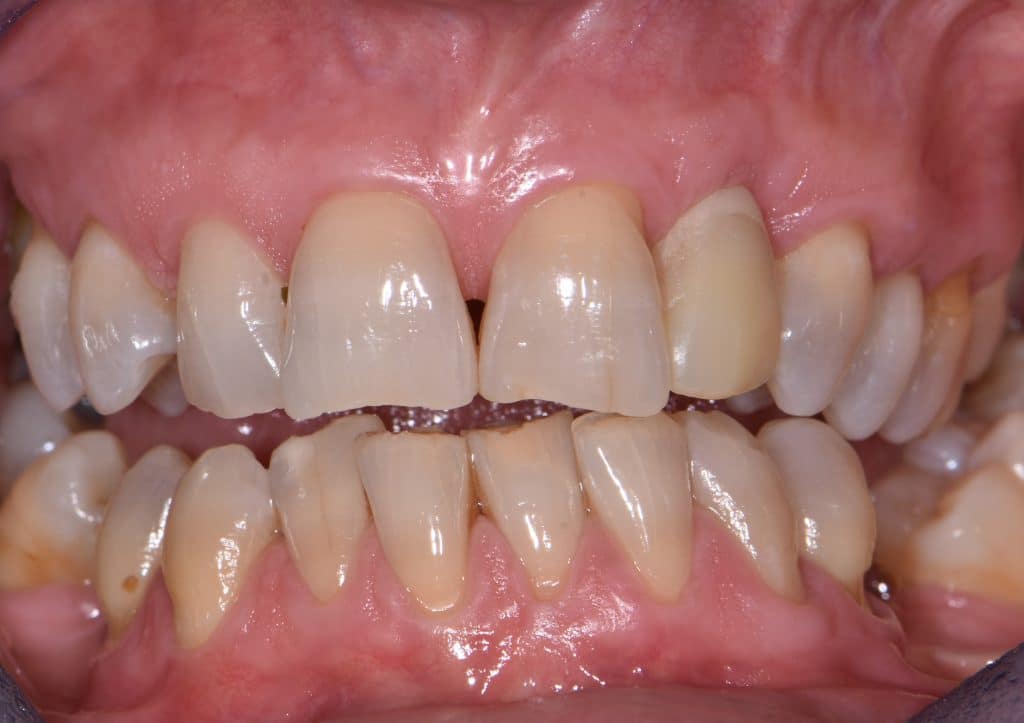

La pz N.G. di anni 52 (ASA 1) viene visitata nel mese di settembre 2017 per la mobilità ed inestetismo dell’elemento protesico 22, (foto iniziali sequenza 1) si evidenzia una frattura parziale della radice, si decide per l’estrazione ( foto sequenza 2) e sostituzione dell’elemento con un restauro implanto-protesico. Purtroppo la scarsa quota ossea apicale all’alveolo post-estrattivo (foto 2 rx) e l’alta valenza estetica dell’elemento ci rende cauti e si programma una socket preservation post estrattiva con l’ausilio delle membrane di prf (foto prf e socket sequenza 3 e 4). Durente i 5 mesi di guarigione la pz porta una protesi parziale mobile (foto 5,2) , a guarigione del sito post estrattivo si evidenzia una buona conservazione dei volumi osseo-gengivali,(foto guarigione sequenza 6) se pur presente una recessione distale all’elemnto 21.Nel mese di febbraio 2018 si procede all’inserimento di un impianto max-stability 3,75x12mm disegnando un lembo anticipato palatino per consentire un aumento dei tessuti vestibolari suturando con tecnica rool flap e trasformando l’elemento parziale mobile in una corona singola a carico immediato sul moncone temporameo applicando i concetti protesici bopt , (foto impianto moncone protesi provvisoria sequenza foto 7-8-9). Durante il periodo di maturazione dei tessuti molli vengono apportate opportune modifiche ai profili del provvisorio al fine di dare maggior spazio al tessuto gengivale, ( fotosequenza 10).Dopo circa 2 mesi dal protesizzazione provvisoria si è proceduto alla realizzazione del manufatto protesico con tecnica chair side sirona con l’ausilio del t-base (foto sequenza 11-12-13), realizzando in una sola seduta una corona in disilicato, ottenendo un risultato più che soddisfacente (Foto 14). Nel controllo a 3 mesi dal carico definitivo si apprezza la perfetta conservazione dei livelli ossei e gengivali. (foto sequenza 15).concludo con un follow up a 18 . Tengo a sottolineare che un caso come questo è stato conducibile con buoni risultati solo grazie alla piena fiducia della pz e alla sua massima motivazione e collaborazione. Ad oggi la pz sorride soddisfatta del risultato. E questo rappresenta la massima ricompensa di chi dedica tutto se stesso alla professione.

rx follow up 18 month post loading